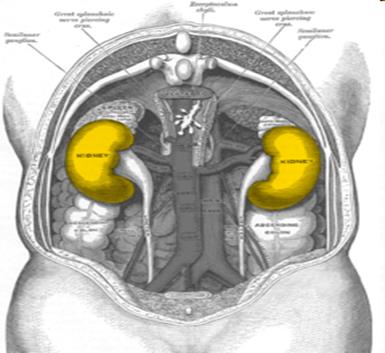

La nefritis es una inflamación del riñón. Término del idioma griego nephro- "del riñón" e -itis "inflamación". Es frecuentemente causada por infecciones, toxinas o enfermedad autoinmune.